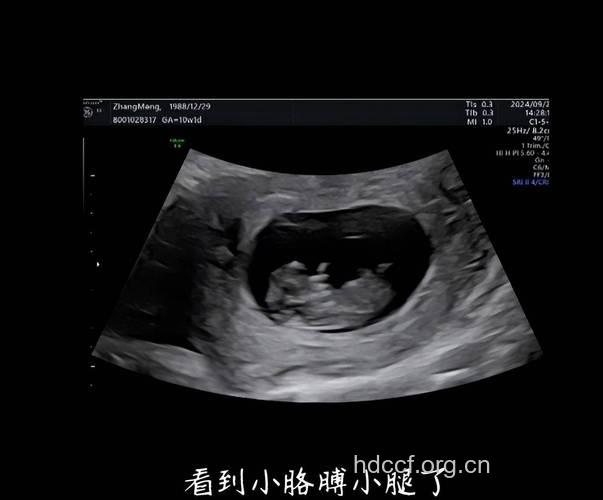

生男生女,其实很早就已经定型,比如说,男孩子在怀孕两个月前是长型的,女孩子是椭圆或是圆型,后来妈妈想了一个看B超单判断生男生女的方法。从B超单看宝宝性别的具体方法是:

1、7W+1D的BC数据: 胎囊2.9*1.9 生的是男孩。

2、9W+4D的BC数据: 宫内见46.6*30.2mm孕囊双胞胎都是女孩。

3、60天的BC数据: 孕囊大小是3.6*1.6MM 生下的是帅哥。

4、5W+6D。孕囊:25mm*11mm 男孩。

5、数据:胚囊:23x17x16 生下的是小美女。

6、46天BC数据:孕囊:20*17*17 女孩。

7、7w+1D的BC结果:32*20mm妊娠囊女孩。

8、8周时是1.6×1.7 生下的是千金。

9、8周的时候是41*28MM 生下的也是女宝宝。

10、8周多是的BC,胎囊是19MM*10MM 后来BC照出来也是男宝宝。

11、胎囊:35mmX34mmX28mm 可爱的女宝宝。

12、孕囊大小:(长)18MM X(宽)16MM X (厚)8MM 今年四月份生的粉可爱女宝宝。

13、62天:内见孕囊2.6*1.8 生的是可爱的男宝宝。

14、50天,孕囊35MM*27MM 生的是女宝宝。

15、孕囊33*18 现B超是男宝宝。